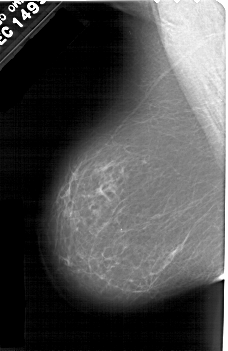

A_1601_1.LEFT_CC

LEFT_CC LINES 5491 PIXELS_PER_LINE 3541 BITS_PER_PIXEL 12 RESOLUTION 43.5 NON_OVERLAY

FILE: A_1601_1.RIGHT_CC.OVERLAY

TOTAL_ABNORMALITIES 1

ABNORMALITY 1

LESION_TYPE CALCIFICATION TYPE PLEOMORPHIC DISTRIBUTION LINEAR

ASSESSMENT 4

SUBTLETY 2

PATHOLOGY BENIGN

TOTAL_OUTLINES 1

BOUNDARY